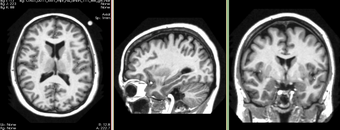

Brain mask as contour